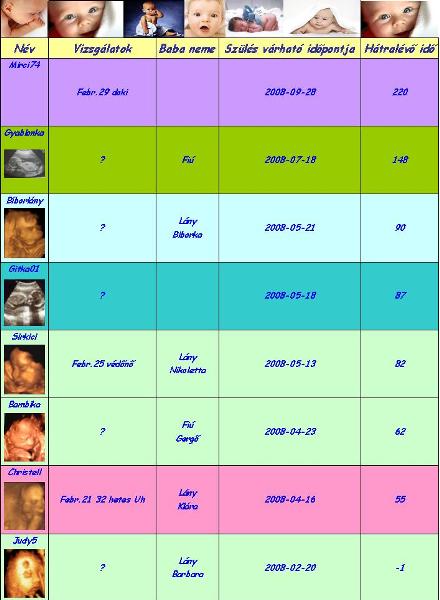

Judy,

úgy látszik Barbika nagyon jól érzi magát odabenn!